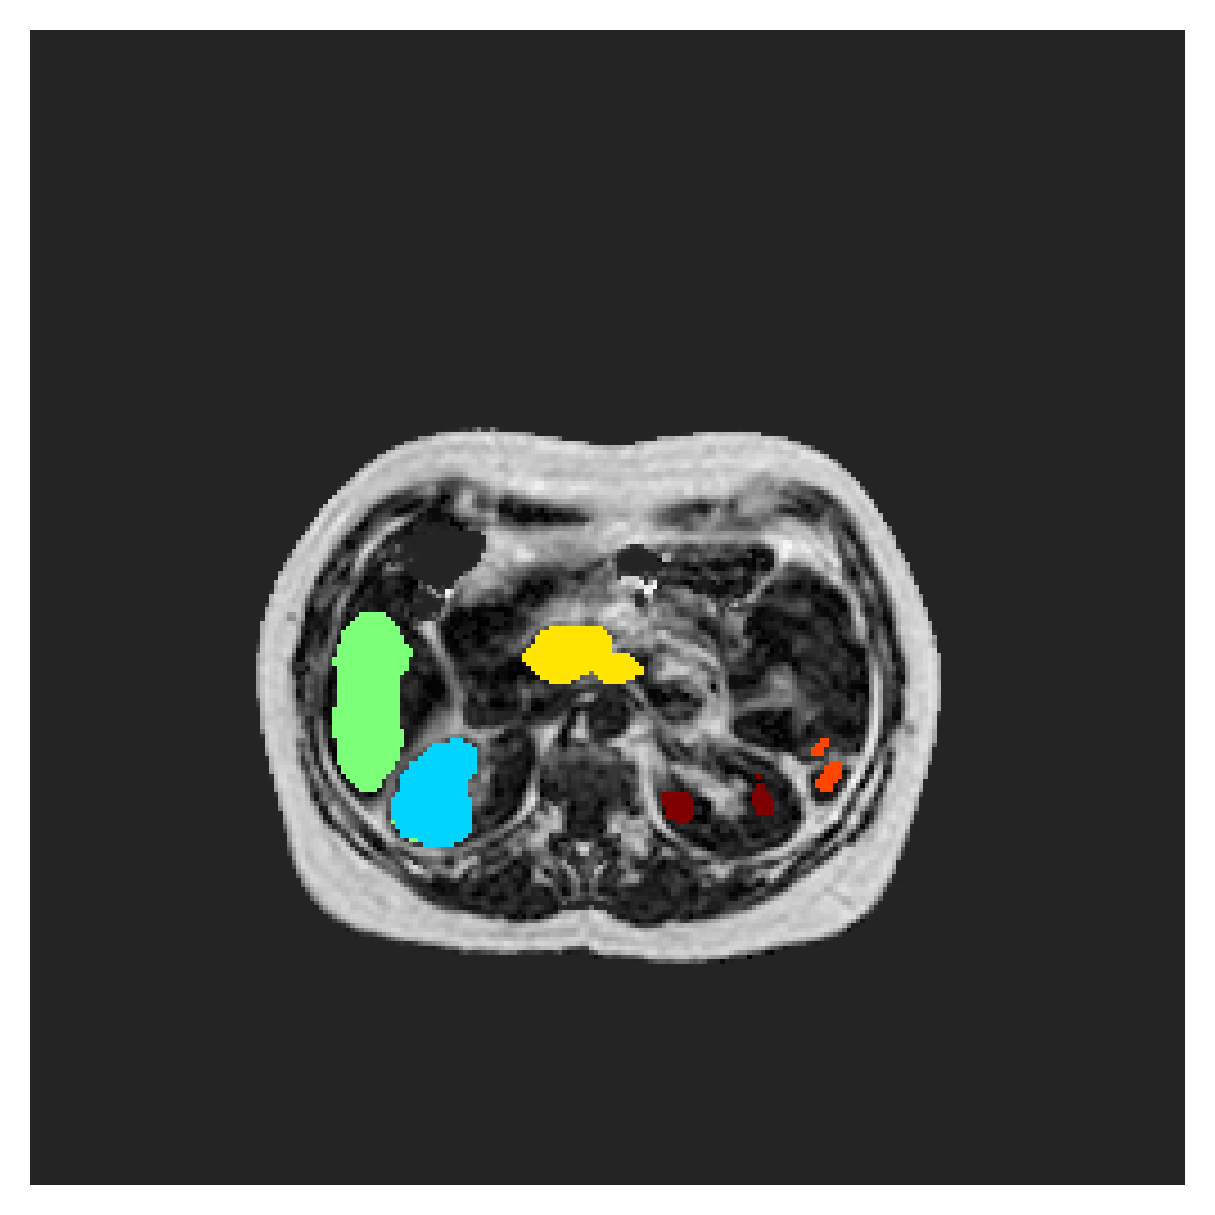

POEM

The Prospective investigation of Obesity, ENergy production and Metabolism (POEM) is a local (not currently publicly available; PI: L. Lind, see [22] for details) cohort of whole-body fat/water separated MR images. Full annotations of the liver, kidneys, bladder, pancreas and spleen are available for 50 subjects, providing a challenging segmentation dataset with heavily imbalanced classes of varying shapes. The resolution of the data is anisotropic, with reconstructed voxel size of in left-right, anterior-posterior and foot-head directions, respectively. For additional technical details regarding the acquisition and specifications of the images see [22].

The images contain two channels, one for water and one for fat content. For training, we normalize the volumes (per channel) and use 2D slices in the coronal plane, sized . The weak annotations are created synthetically, following the same procedure as described for the ACDC dataset.